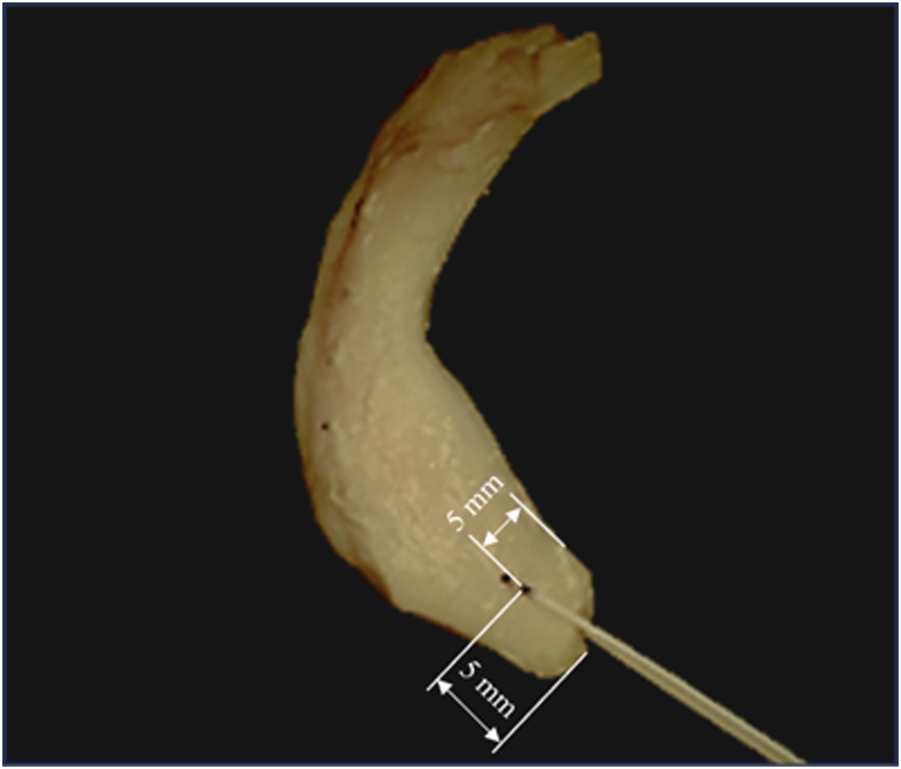

At the time of testing, a N°2 non-absorbable, high-resistance, 100% UHMWPE, braided fiber thread (Force Fiber® No. 2, Stryker Iberia, Madrid, Spain) was inserted by a specialized surgeon in the meniscal horn at 5 mm from both its internal edge and its root junction (Figure 1), using the attached ½ circle tapered needle. The puncture point was selected to match the zone where the surgical hole is normally made during the surgical procedure (Kim et al., 2006; Moon et al., 2010). The thickness of the meniscus at the insertion point was measured with a manual caliper.

FIGURE 1

FIGURE 1. Sutured meniscus with N°2 non-absorbable, high resistance, 100% UHMWPE, braided fiber thread at 5 mm from its internal edge and its root junction. Marks are shown in an intact specimen that was discarded for not meeting the inclusion criterion.